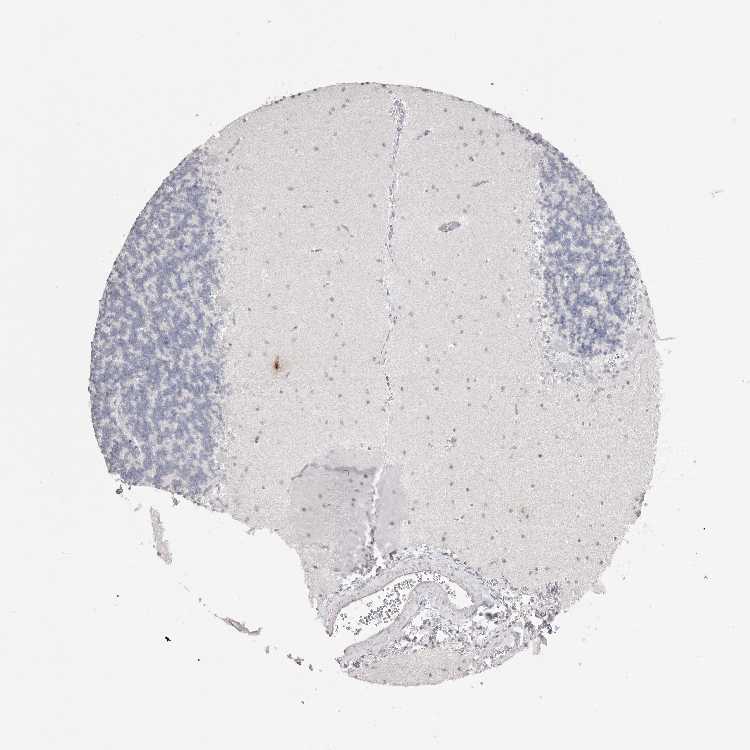

BRAIN CEREBELLUM Show tissue menu

CEREBELLUM - Expression summary

CEREBELLUM - Antibody stainingi

Antibody staining in the annotated cell types in the current human tissue is reported as not detected, low, medium, or high, based on conventional immunohistochemistry profiling in selected tissues. This score is based on the combination of the staining intensity and fraction of stained cells.

Each image is clickable and will lead to virtual microscopy that enables deeper exploration of all samples and also displays staining intensity scores, fraction scores and subcellular localization as well as patient and tissue information for each sample.

Antibody HPA008943Antibody HPA009083Antibody CAB025178

Purkinje cells HighMediumNot detected

Cells in granular layer LowLowNot detected

Cells in molecular layer MediumLowNot detected